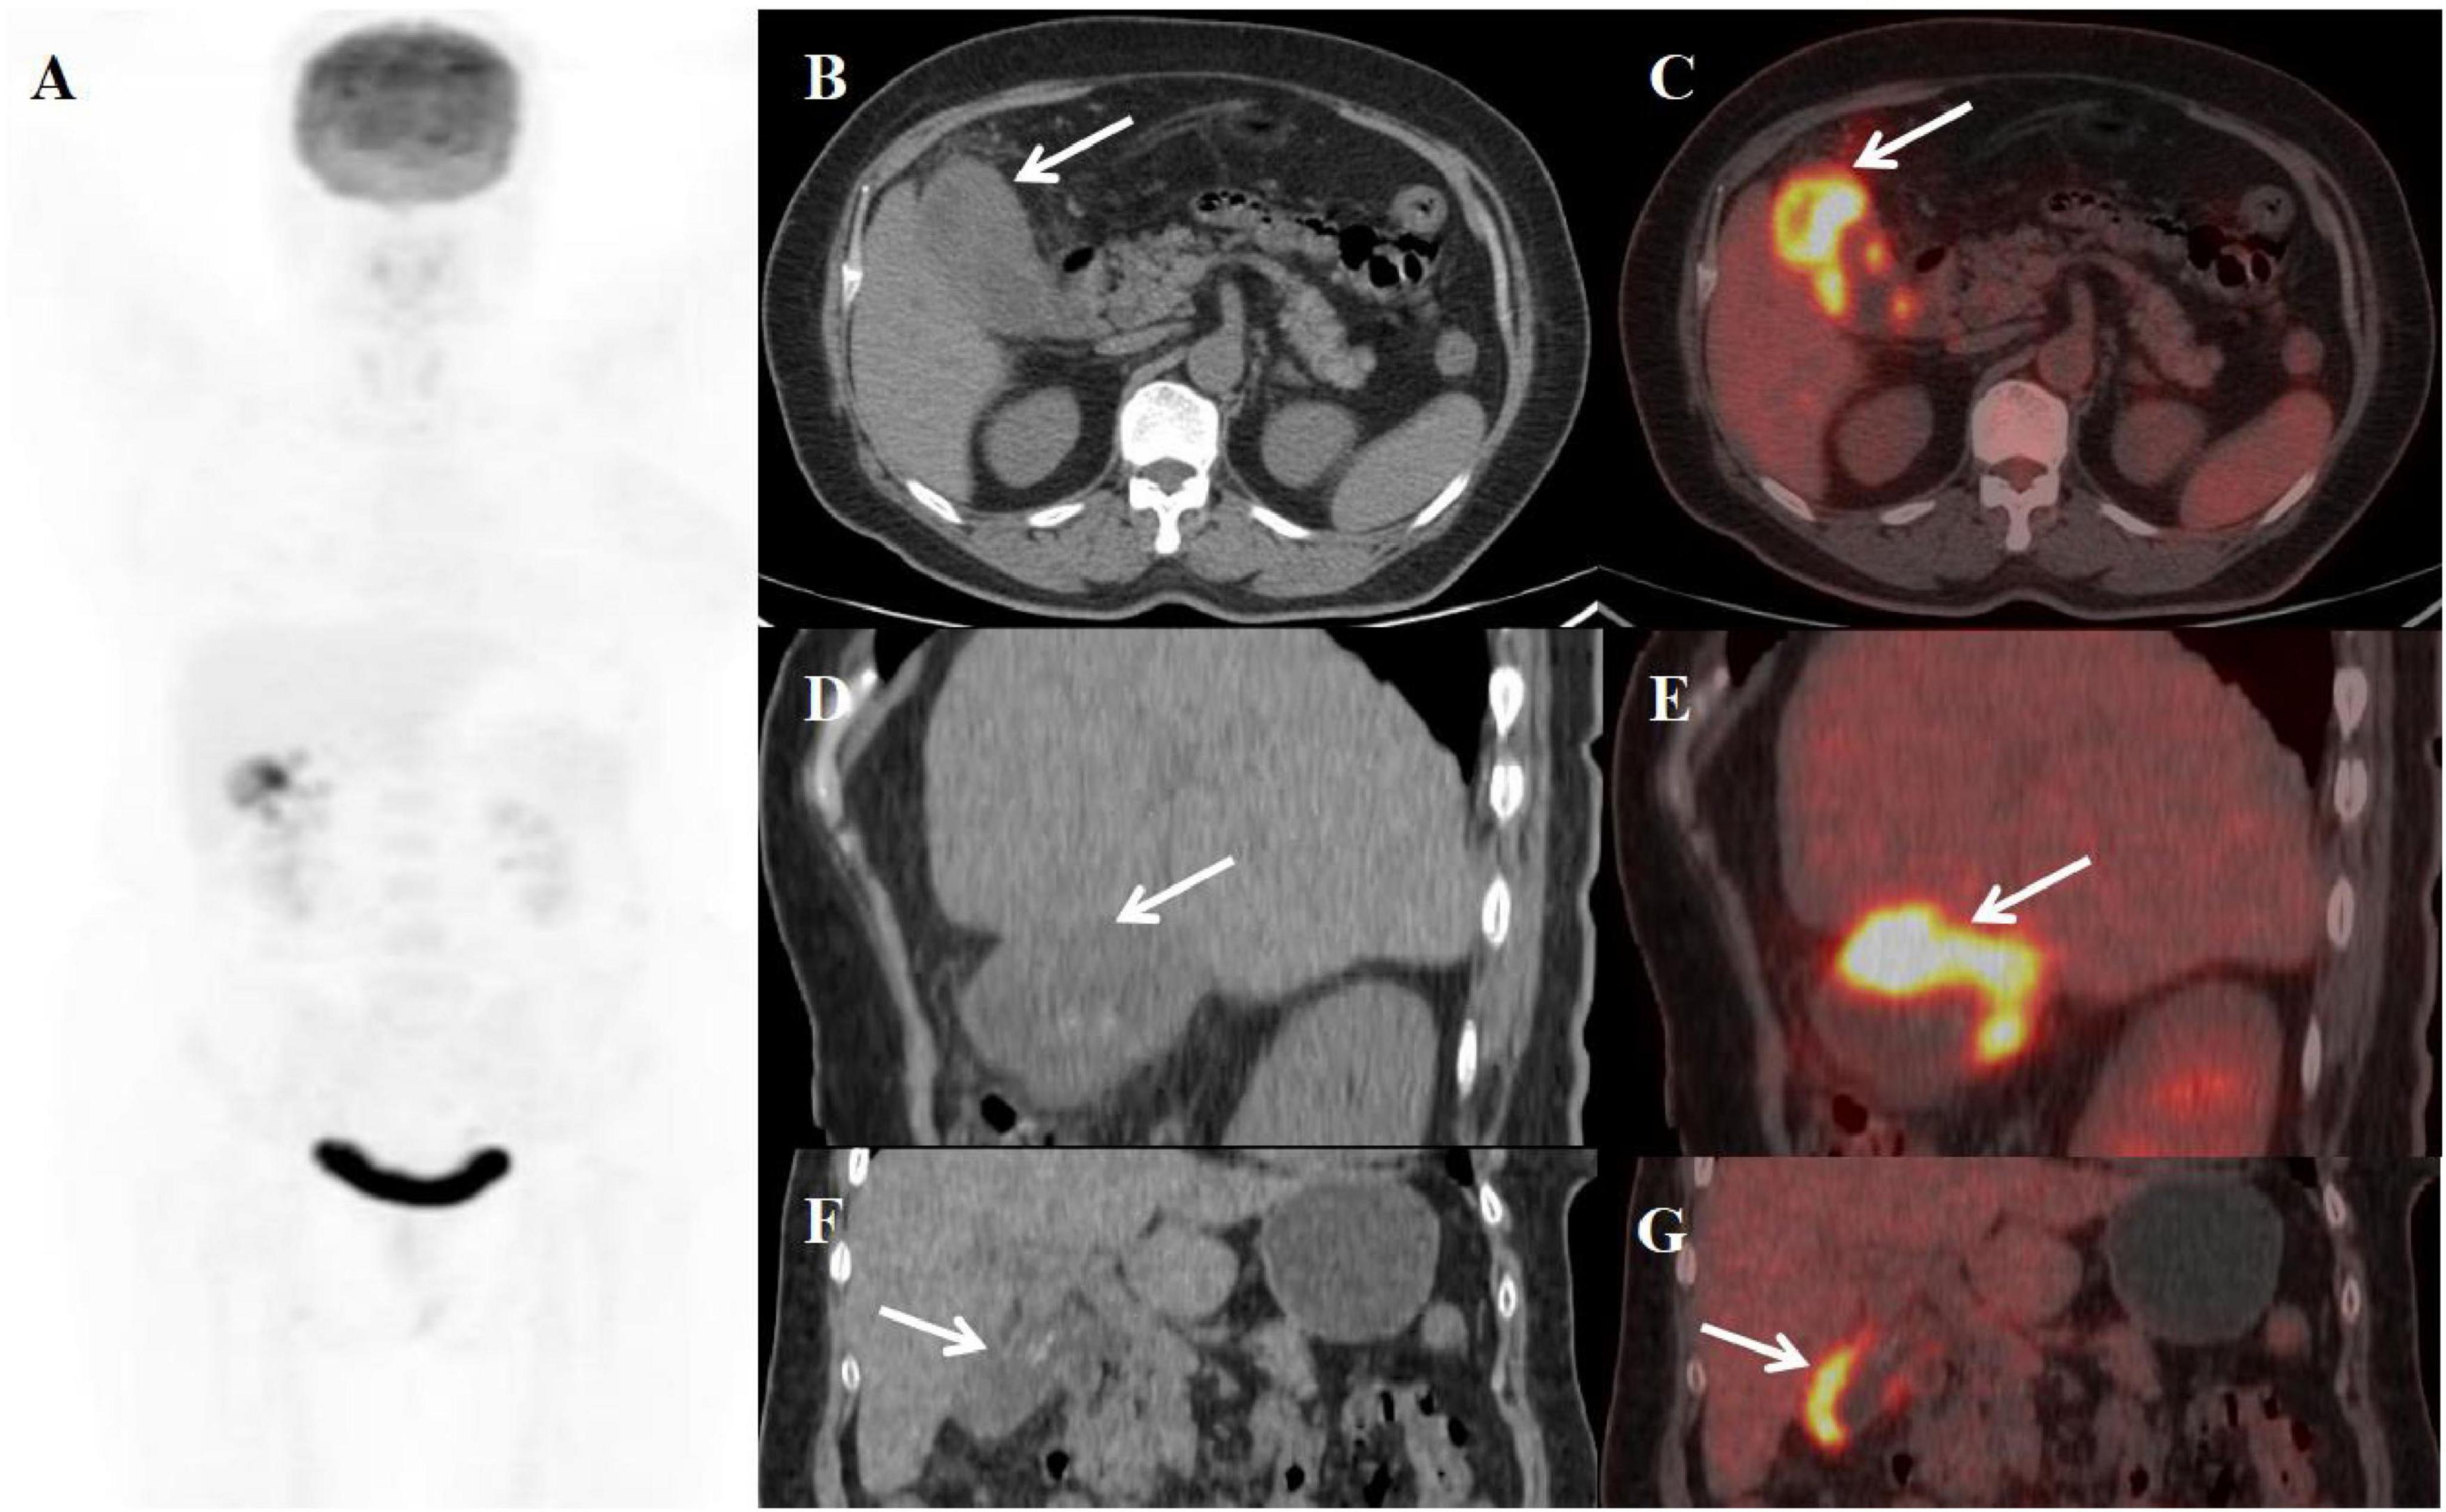

A 59-year-old female presented with abdominal pain for two weeks. Physical examination revealed a positive Murphy’s sign. The patient had a history of breast cancer surgery. Initial laboratory findings demonstrated moderate leukocytosis (WBC 12.50 × 109/L) with neutrophilic predominance (81%). Additionally, elevated inflammatory markers were observed, including C-reactive protein (CRP: 13 mg/L) and a mild increase in carbohydrate antigen 19-9 (CA19-9: 70.51 U/mL). All other tumor markers were within normal limits. Abdominal ultrasonography and MRI performed at an outside hospital demonstrated gallbladder wall thickening with multiple intraluminal gallstones. Given the clinical presentation, gallbladder malignancy could not be excluded, prompting referral to our institution for PET/CT evaluation. The PET/CT scan demonstrated an enlarged, adherent gallbladder with diffusely irregular wall thickening (maximum 12 mm) containing intramural hypodense nodules. The lesion showed intense FDG avidity (SUVmax 19.8) while maintaining mucosal integrity, though with loss of the normal hepatobiliary interface. Additional findings included inflammatory changes in pericholecystic fat and enlarged retroperitoneal lymph nodes (Figure 2). These features were initially interpreted as consistent with advanced gallbladder carcinoma with hepatic invasion and nodal metastasis. The patient subsequently underwent definitive surgical management including open cholecystectomy with partial hepatectomy. Final histopathological examination established the diagnosis of XGC, characterized by the hallmark findings of foamy histiocyte aggregates, chronic inflammatory infiltrates, and cholesterol clefts without evidence of malignancy.

Figure 2. Female, 59 years old. (A) (whole body MIP), (B, C) (Axial CT and fused axial PET-CT), (D, E) (Coronal CT and fused coronal PET-CT), and (F, G) (Sagittal CT and fused sagittal PET-CT). 18F-FDG PET/CT Imaging Findings: The gallbladder appears enlarged and adherent, demonstrating diffuse irregular wall thickening (maximum 12 mm) with intramural hypodense nodules (B, D, F, arrow ↑). Significant FDG uptake (SUVmax 19.8) was observed in the lesion, which preserved mucosal continuity despite disruption of the typical hepatobiliary interface (C, E, G, arrow ↑). Accompanying features comprised inflammatory infiltration of pericholecystic adipose tissue and enlargement of retroperitoneal lymph nodes.